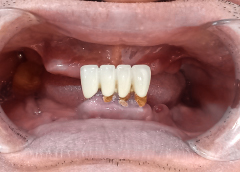

Cô Bạch Thúy

• Mất răng toàn hàm và tiêu xương nặng

Vũng Tàu

Bị mất răng toàn hàm và sử dụng hàm tháo lắp lâu năm không chỉ khiến cô Bạch Thúy ăn nhai khó khăn, mà còn gặp biến chứng tiêu xương nghiêm trọng. Khiến khuôn mặt của cô bị hóp và trông già hơn tuổi thật .

Quyết định cắm răng Implant để thay đổi, cô được người bạn giới thiệu đến nha khoa I-DENT.

Đến I-DENT gặp được bác sĩ Thái tư vấn rất nhiệt tình, đúng tình trạng, đúng nhu cầu của cô, chứ không bày vẽ thêm như những nơi khác. Nên có mới an tâm làm răng ở đây.

Kết thúc quá trình trồng răng cùng bác sĩ Thái, cô Bạch Thúy đã có thể ăn uống thoải mái và tự tin hơn với nụ cười của mình.